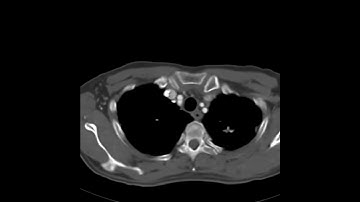

Classic intralobar sequestration on CT.